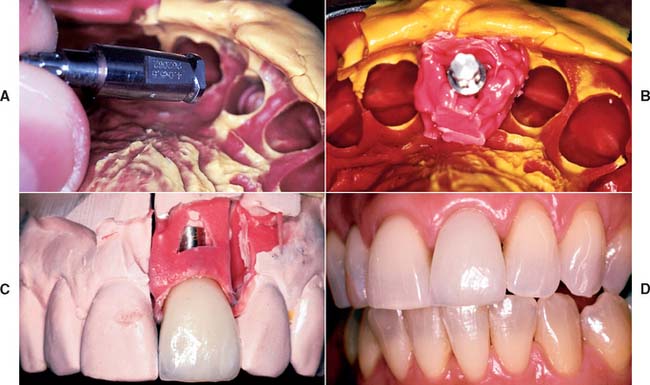

Accurately mounted diagnostic casts (see Chapter 2) are essential for treatment planning. They are used to study the remaining dentition, evaluate the residual bone, and analyze maxillomandibular relationships. They can be helpful to the surgeon for fixture placement. A diagnostic waxing is performed on the cast or on a duplicate. Proposed fixture installation sites are checked for proper alignment, direction, location, and relation to the remaining dentition. The waxing helps determine the most esthetic placement of the teeth to be restored and the potential for functional speech disturbances. After adjustments and the diagnostic waxing are completed, a resin template can be made from the cast to guide the surgeon during implant placement (Fig. 13-9). Diagnostic waxings and surgical templates are essential when implants are planned as part of a full-mouth reconstruction or when the anterior esthetic zone is restored (Fig. 13-10).

Fig. 13-20 Anterior implant placement with a surgical guide template. A, The apical extent of the template is not removed, which allows the superoinferior orientation of implant placement to be determined. B, Full-thickness flap incisions are made, preserving the interdental papilla. The flap is reflected to expose bone for preparation of the implant site. C, Resin (2.0 mm) has been added to the lingual aspect of the matrix; the rest of the lingual area was left open so the surgeon can choose the best available bone. The site should be prepared as close to the template as possible. D, The implant is positioned 2.5 to 3.0 mm apical to the desired emergence position of the final restoration. E, The implant is positioned at an angle and depth that allows optimum esthetics and access for hygiene. F, The surgical site is sutured. A 4 to 6-month healing time is allowed.

(Courtesy of Dr. J. A. Holloway.)